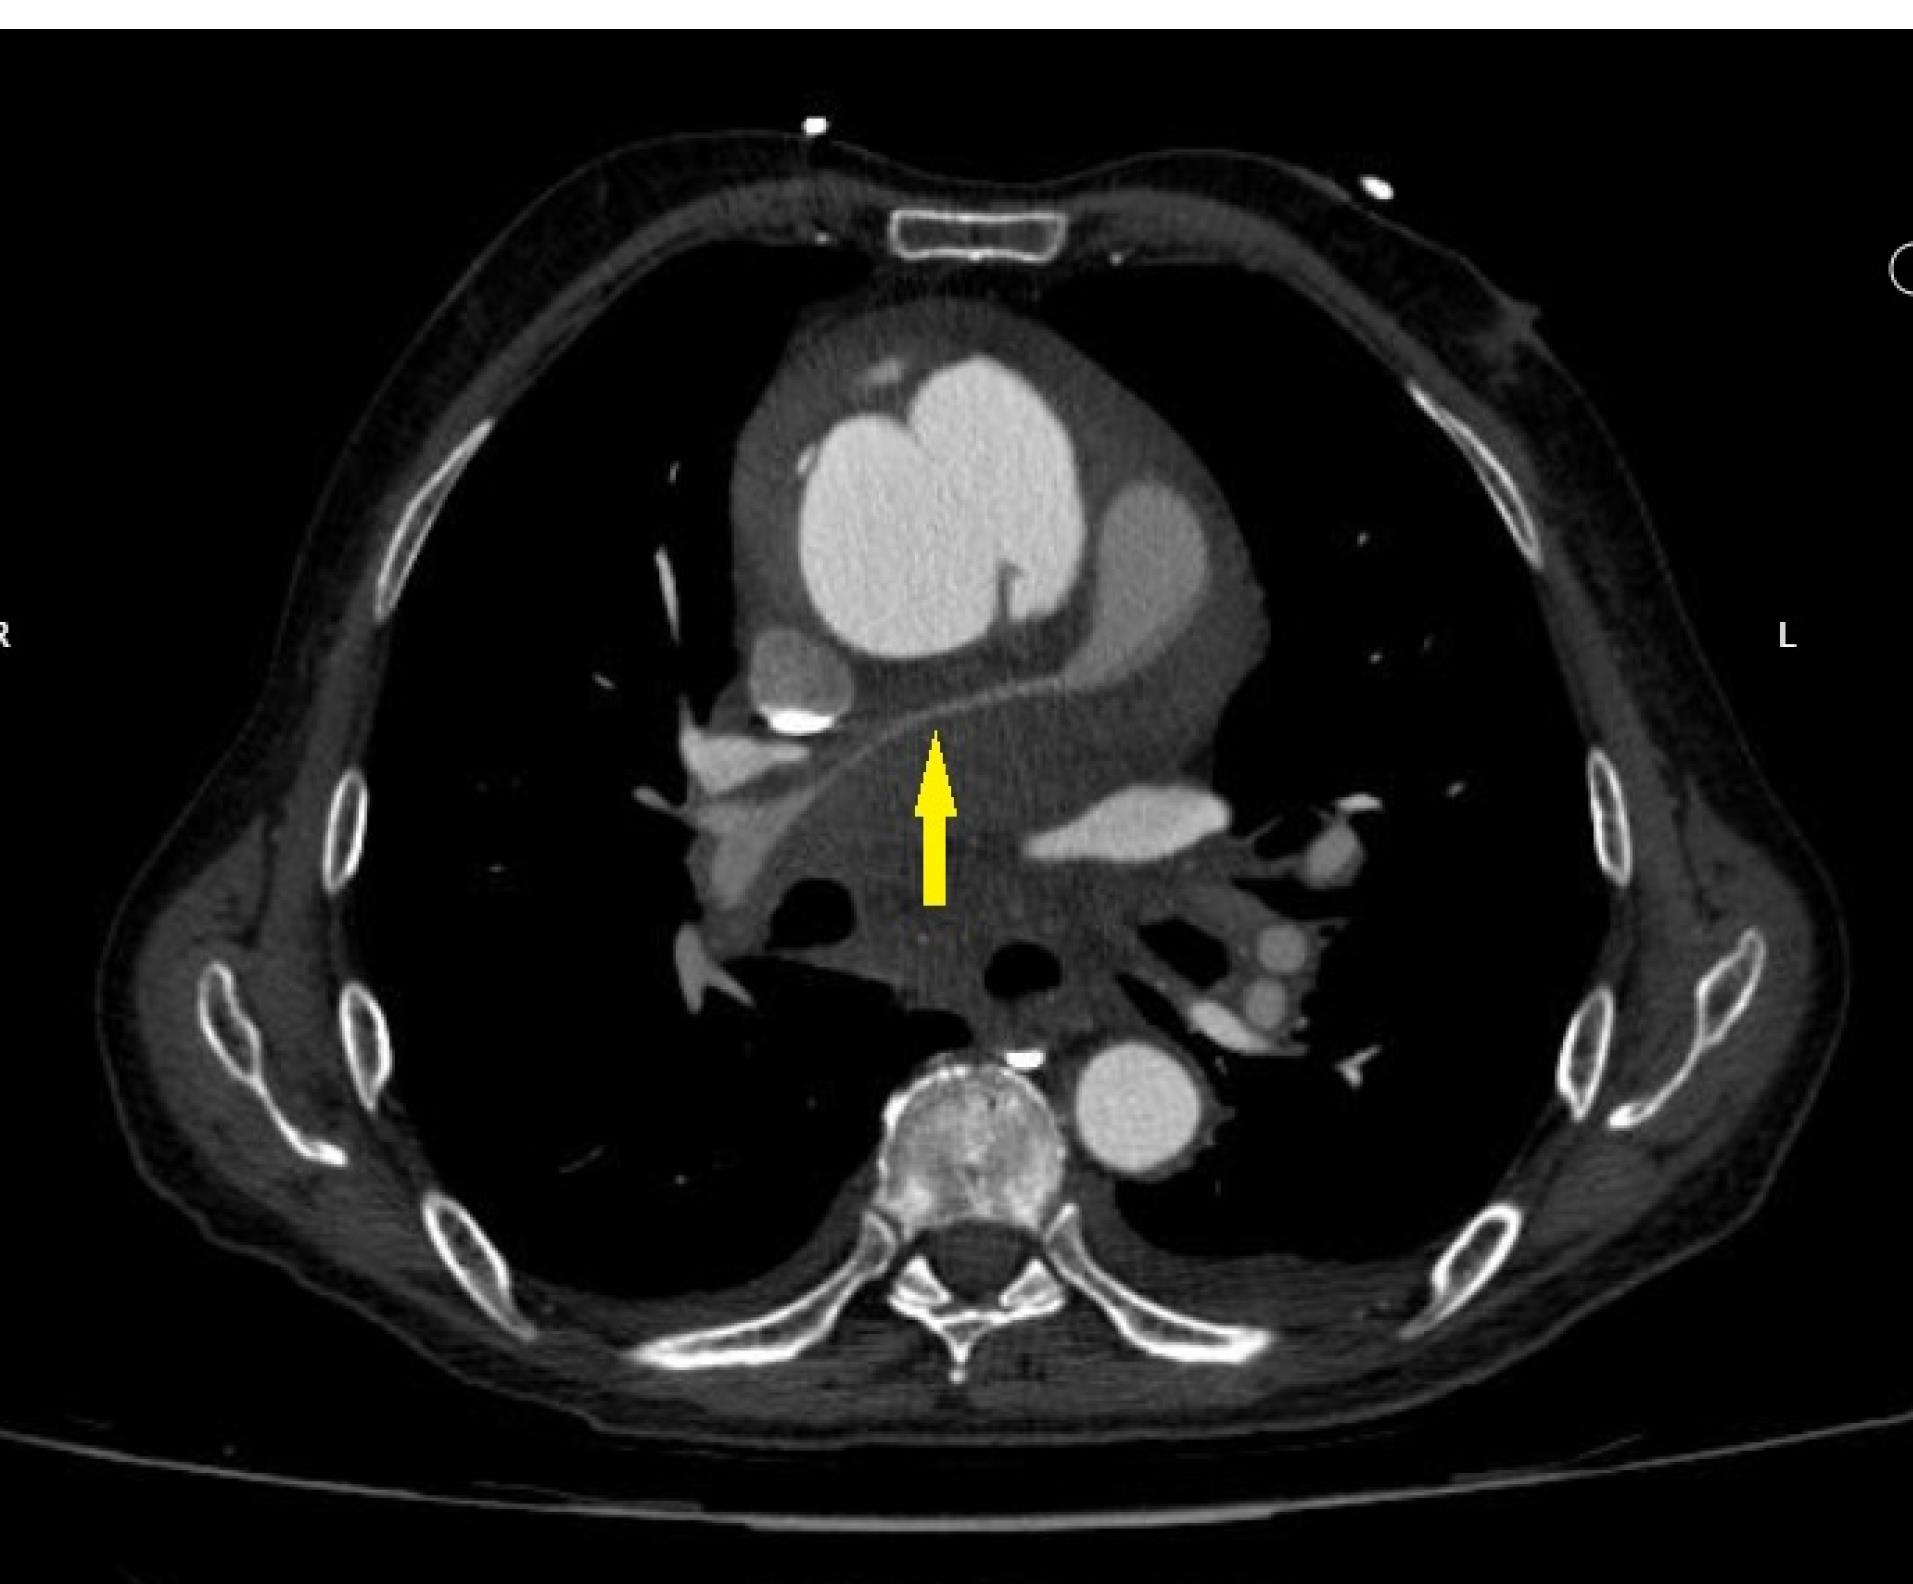

For better evaluation of aorta, thoracic and abdominal aortic computed tomography (CT) angiography was done which supported echocardiographic findings. Ascending aorta was dilated with 70mm diameter. The double lumen aorta with intra-mural contrast, confirmed a type A aortic dissection with 14mm thickness of hematoma. Suspicious evidence of contrast extravasation around dissected aorta was seen. Severe compressions of the distal main and right pulmonary artery by hematoma were seen (Figure 3). Emergent cardiac surgery consult was done and the patient underwent surgery in another center. The Bental surgery was done and the diagnosis was confirmed through the surgery. Due to severe right ventricle systolic dysfunction, the patient’s extubation was very difficult. The patient died ten days after the operation due to multiorgan failure.

Figure 3.

Spiral contrast-enhanced chest CT shows the double lumen aorta with intra-mural contrast, diagnostic for aortic dissection. The main and right pulmonary arteries are compressed by hematoma of type A aortic dissection (yellow arrow)